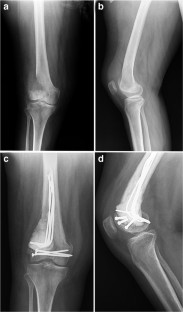

Fig. 3